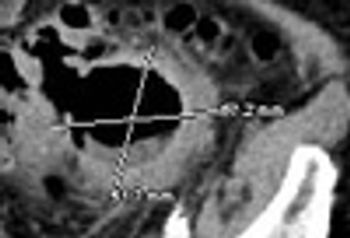

A Case of Giant Colonic DiverticulumPublished: December 14th 2011 | Updated: